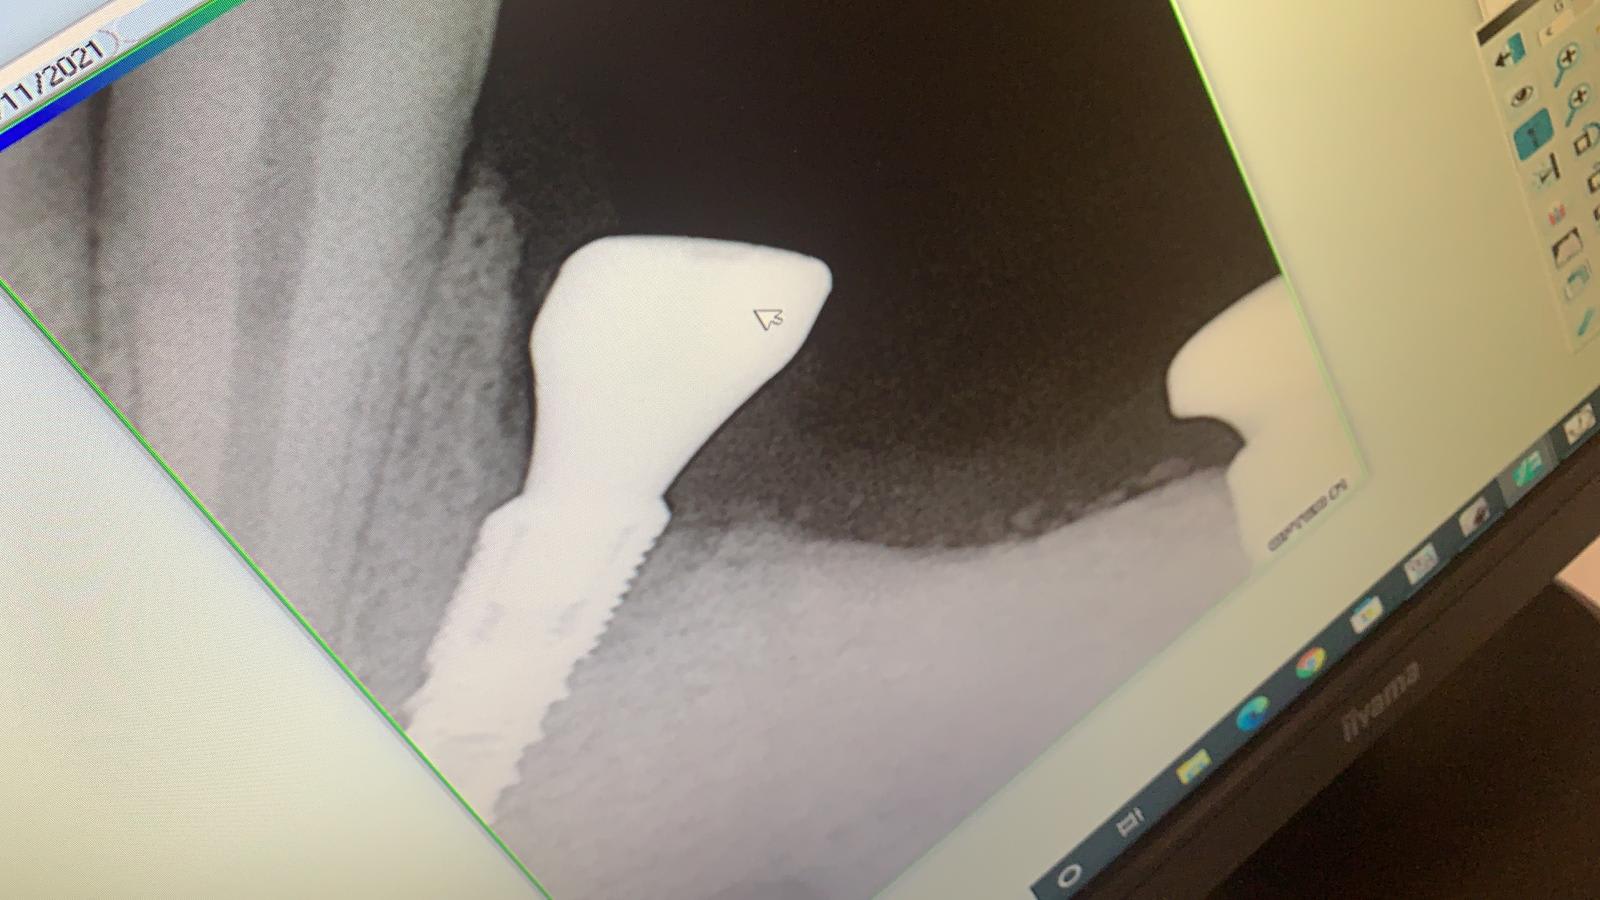

mon référent implanto a poser 2 implants ETK en lieu et place de 34 et 36.

Je vous envoie la radio ,j'ai un doute pour la gestion de la 34. n'ya t-il pas un risque avec ce pan osseux mésial?

Je n'ai jamais été confronté à une telle situation.

Edit : Dans un cas similaire, un pan osseux ne me permettait pas de visser le transfert. Donc si tu peux faire ton empreinte et que le profil d'émergence de ton pilier est similaire à celui de ta vis de cicatrisation, tu ne devrais pas avoir de problème.

Je dirais non.

Il vaut mieux trop d'os que pas assez.

Il avait fait une MCI ?

Extraction, Implantation immediate.